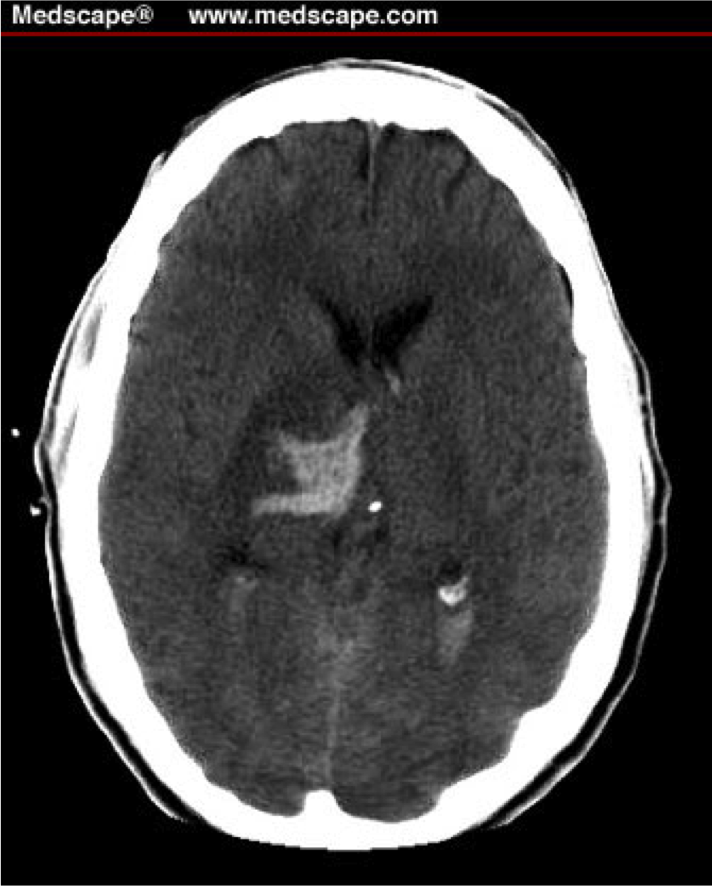

What is shown?

Bleed in ventricular system